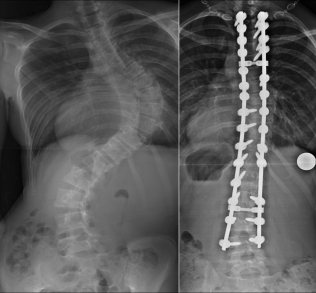

Left: 3-year-old boy with infantile scoliosis. Right: same boy 2 years after implantation of a non-stiffening implant. The spine can thus ideally be controlled and slowly partially corrected until the completion of spinal growth.